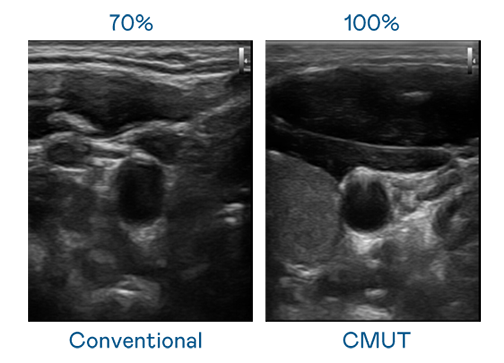

CMUT 技术是一种用电容式微机电元件来产生超音波讯号的技术。与传统 PZT 压电式技术相比,CMUT 频宽增加 30%,更宽频的超音波讯号让影像解析度大幅提升,是实现高影像品质医疗超音波扫描、促进精准医疗发展的关键技术。

超音波影像的解析度高低,首先取决于探头能发出的讯号频宽。爱游戏体育 CMUT 可提供高清晰的超音波讯号,提供高频宽、高灵敏度、影像纹理细节更高的超音波影像,协助医护人员缩短影像判读时间及利用精准的医疗影像进行诊断。